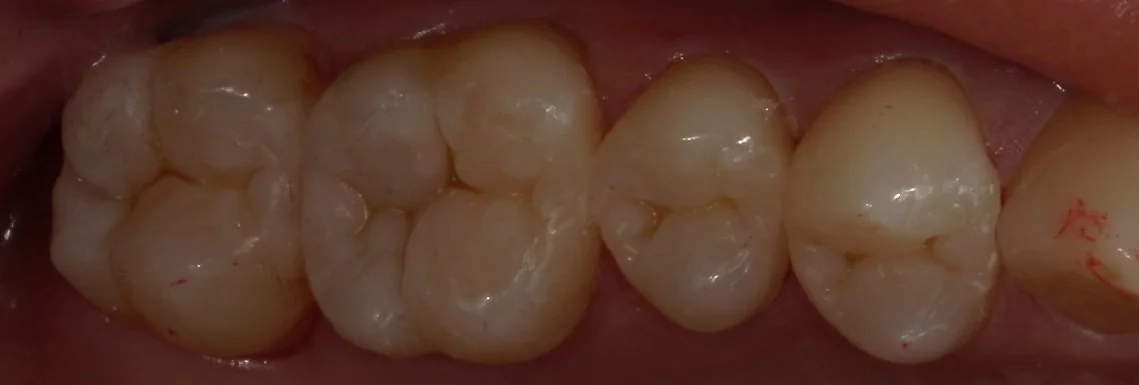

さて、詰め終わったのがこちらになります。

違和感なく綺麗に詰められたかと思いますヽ(゚∀゚)ノ パッ☆

左から2番目が非常に大きかったので、今後痛みが出ないことを祈るだけですね・・・。

患者さんからは「歯が新品になったみたい!」って言って喜んでいただけました。

今回は遠方からの方なので、纏めて4本一気にやっていますが、基本的には疲れすぎるので2本ずつ行うことが多いです(;・∀・)